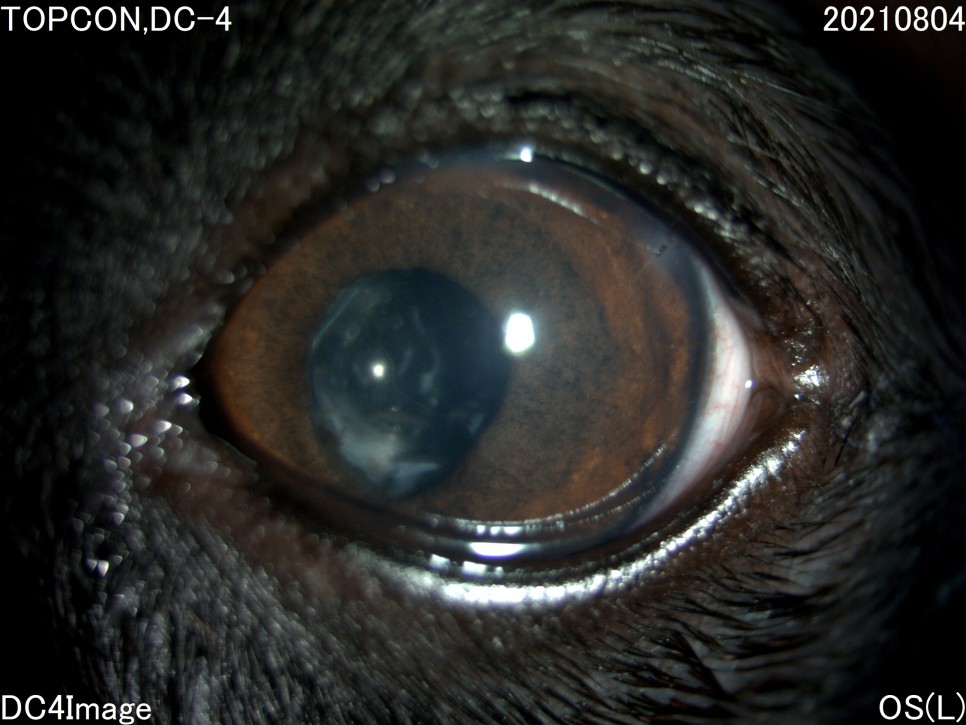

- 세극등 현미경 검사

양안의 백내장이 심하게 진행되고 있었지만 다행히도 당뇨병 관리를 하고 있는 전주 24시 동물병원은 당뇨병 관리 뿐만 아니라 눈 관리도 계속해 주셨기 때문에 내원 당시에는 양안 모두 심한 포도막염은 없었습니다.

그러나 왼쪽 눈은 백내장 단계 중 4기인 과성숙 단계로 진행되었으며, 이전에 앓고 있던 심한 포도막염에 의해 홍채의 일부가 수정체에 유착되어 있는 것이 보였습니다.

백내장이 오래 되거나 염증 반응이 심한 경우는 수정체를 감싸는 낭포 섬유화가 일어나 낭 자체에 백내장 파편이 붙어 있을 수 있는데, 자녀분이 바로 그런 상태였습니다.이런 경우 수술이 어려울 뿐만 아니라 수술 후 합병증의 발생률도 더욱 높아질 수 있습니다.